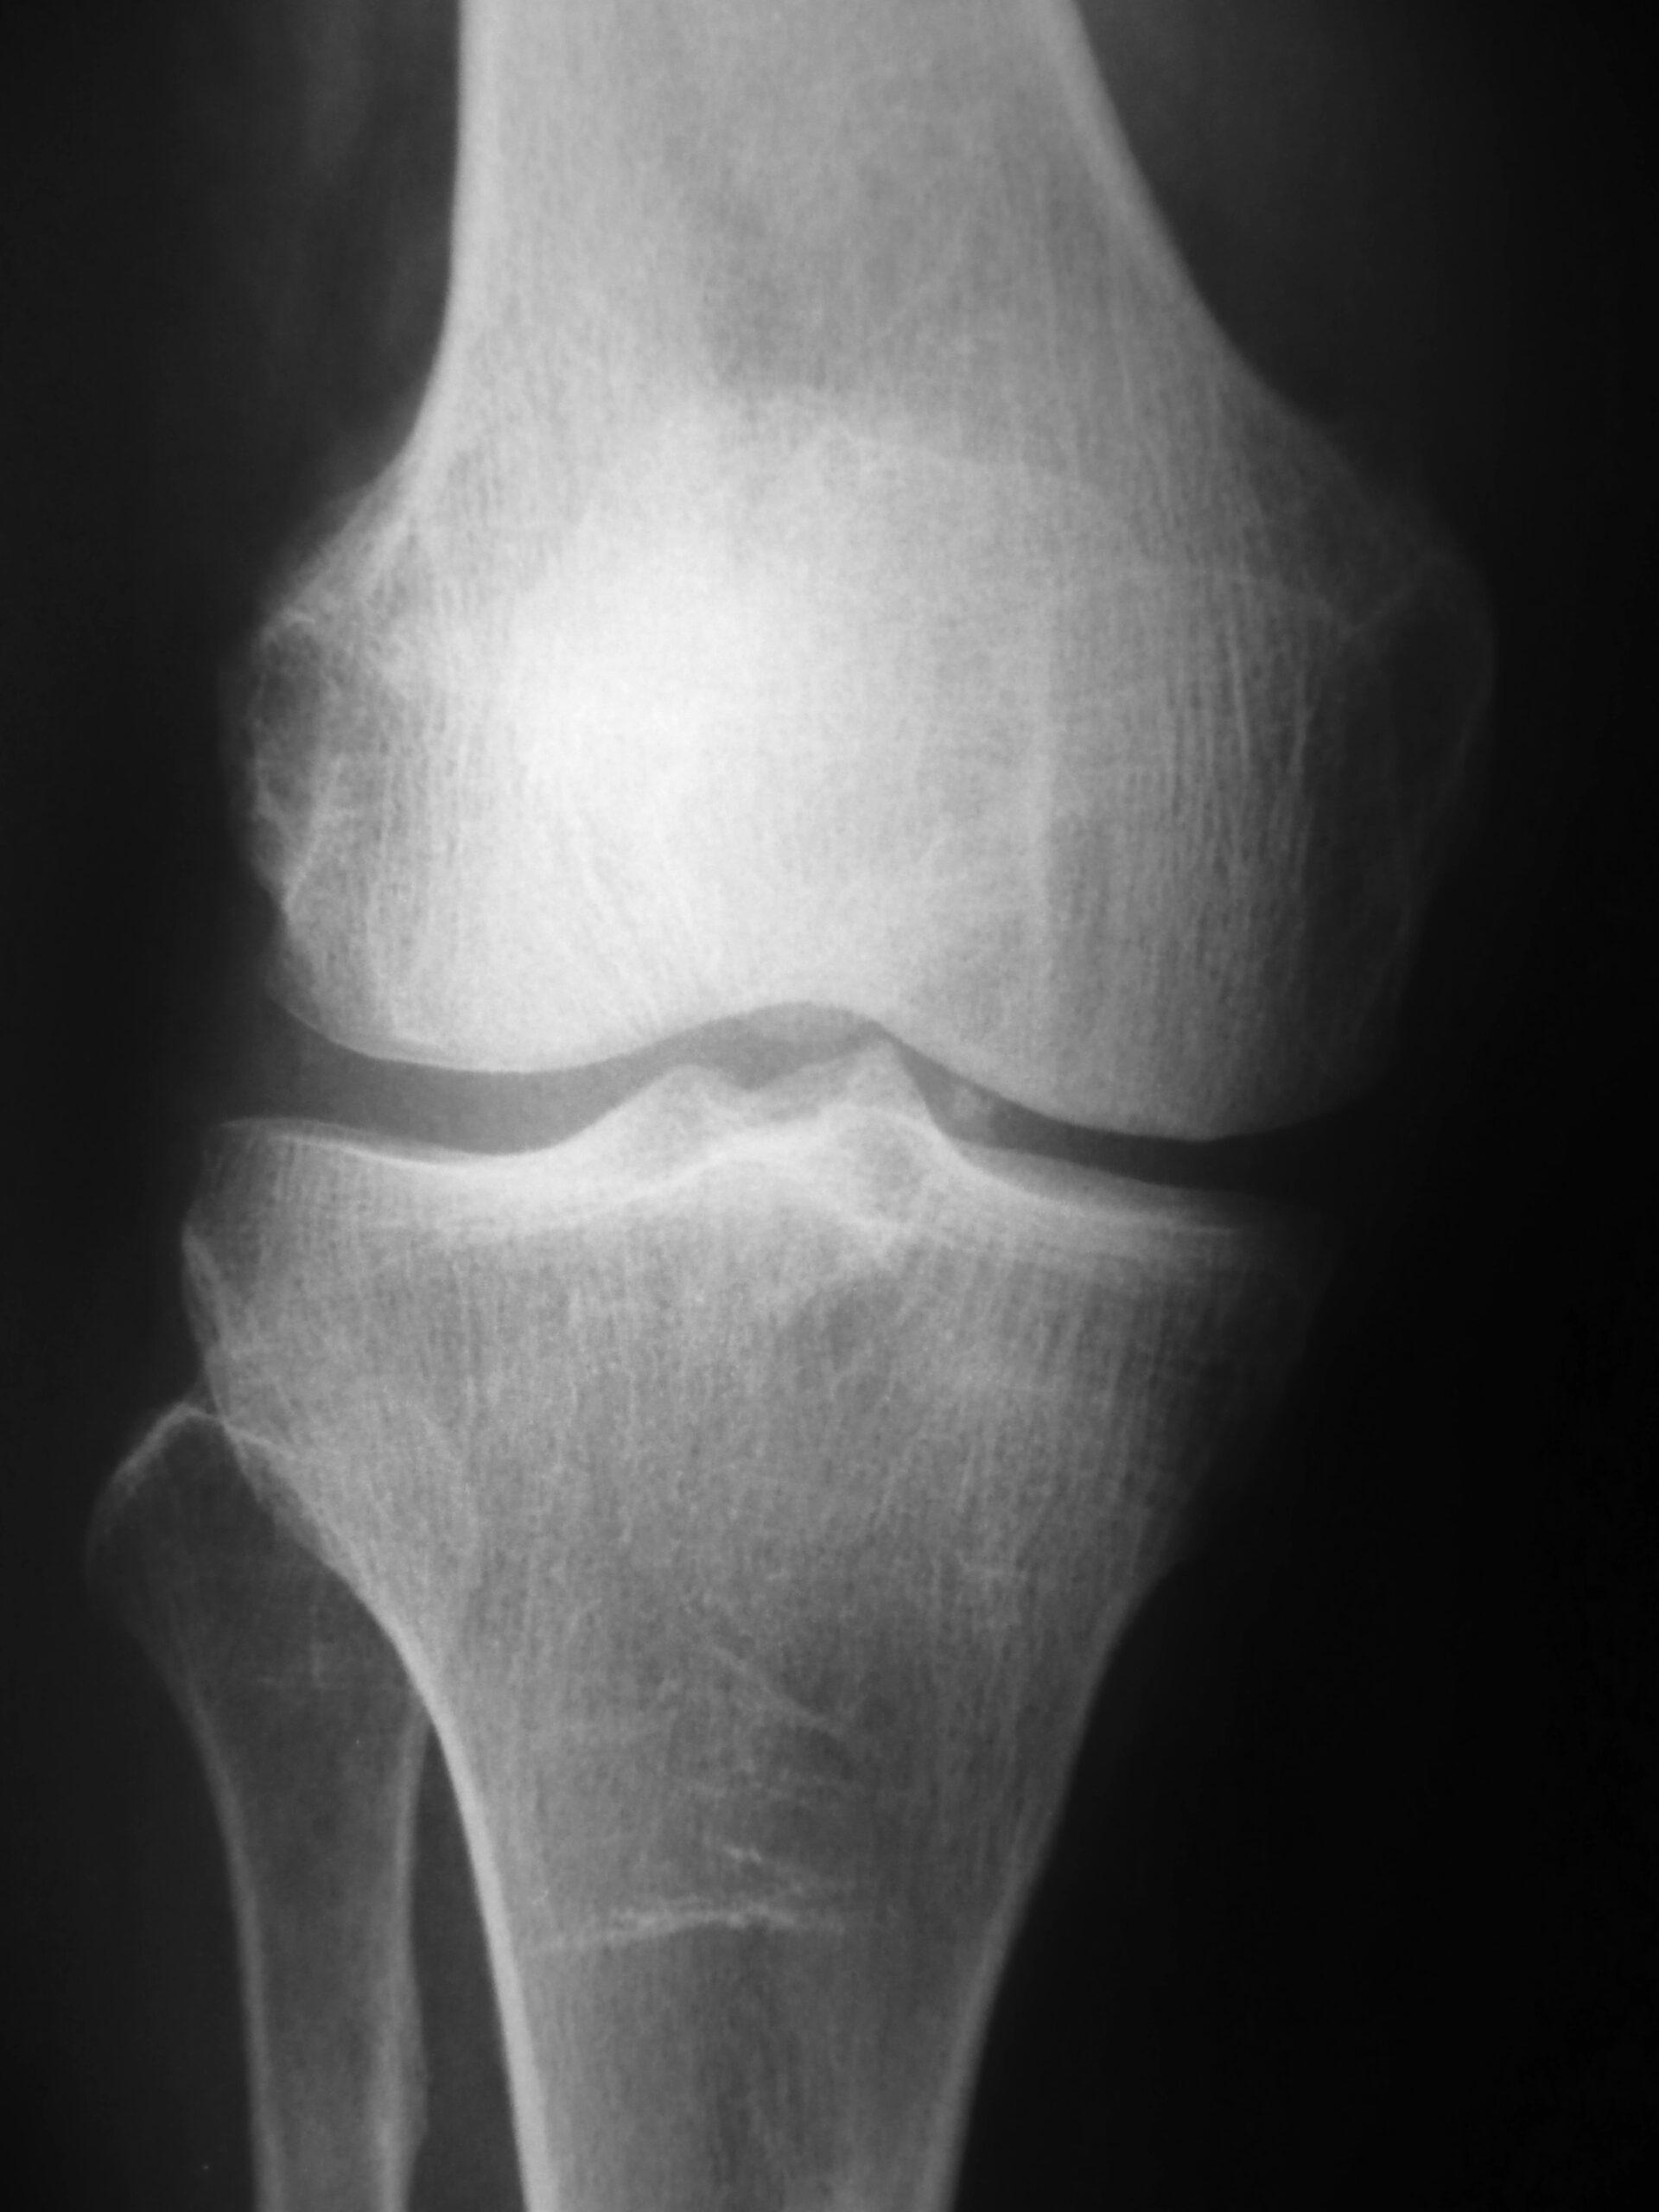

Because some doctor who did not even take the time to listen to their story, only looked at an x-ray of their

knee said their problem was “arthritis” and nothing can be done….Except wait to have a knee replacement. This person leaves scared and confused and searches Dr. Google. What will they find? Thousands of articles, stories, random garbage painting a bleak picture (some will be good- don’t get me wrong). So what does the person do? Sits and waits for the inevitable knee replacement, avoiding once enjoyable activities, taking medication to keep the pain at bay, watching life pass by.

To begin with, understand that “arthritis” is just normal aging of the joints (wrinkles on the inside). Simply because some picture shows changes in a joint does not mean IT is the cause of pain (but doctors will tell you so)….BECAUSE there is BIG money in medication interventions (surgery). This is a cynical viewpoint I know – but that does not mean my assertion is wrong. I cannot begin to tell you the number of stories of individuals who were told they have arthritis when they were not even complaining of joint pain. Just why the #$%^ are doctors telling people this, when if they would actually listen and examine the person, they would know the issue was something else.